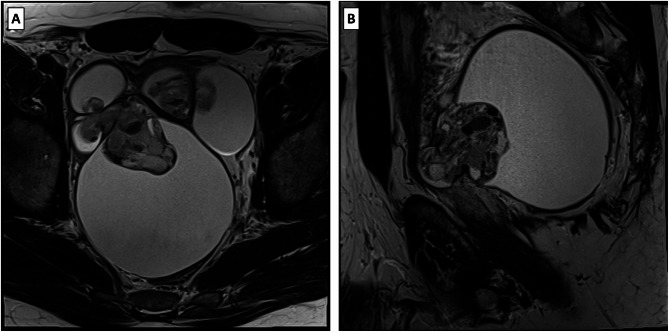

Case presentation: We describe a 45-year-old patient with chronic pelvic pain and obstructive urinary symptoms. Imaging revealed a large cystic and solid mass involving his seminal vesicles, with significant mass effect on adjacent structures. Differential diagnoses included seminal vesicle adenocarcinoma and sarcoma. Complete surgical resection and subsequent histopathological analysis confirmed a low-grade seminal vesicle MEST with biphasic epithelial and stromal components, lacking atypia or notable mitotic activity. Immunohistochemical analysis revealed stromal positivity for estrogen receptor (ER), progesterone receptor (PR), smooth muscle actin, desmin, and CD34, and epithelial positivity for PAX8, PAX2, CK7, and MUC-6, supporting the diagnosis. The patient remains disease-free 32 months post-surgery.